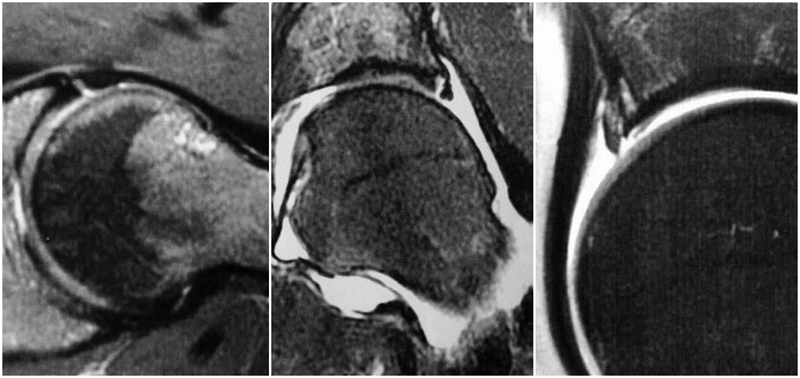

对于髋关节撞击综合征的诊断,不同于髋关节骨性关节炎或者股骨头坏死的患者,不能仅仅通过普通的X光片和双髋关节核磁共振就能确诊,因为造成髋关节撞击综合征的异常骨性凸起通常位于髋臼或者股骨头颈结合区的前外侧,所以临床上常规的髋关节正侧位片上,这个骨性异常的区域恰恰被遮挡了起来,在X光片上成了重叠的影像。在诊断髋关节撞击综合征,会采用一些特殊的影像拍摄方法。对于X光的选择,推荐进行骨盆正位相联合蛙式侧位或Dunn位像。对于盂唇损伤的诊断主要依赖于核磁共振检查,由于双髋关节核磁共振放大率以及扫描方向的问题,不足以判断盂唇的状态,一般需要进行单髋关节核磁共振扫描。

图7 摘自Stoller DW. Magnteic Resonance Imaging In Orthopaedics And Sports Medicine[M]. 3rd Edition, 2007